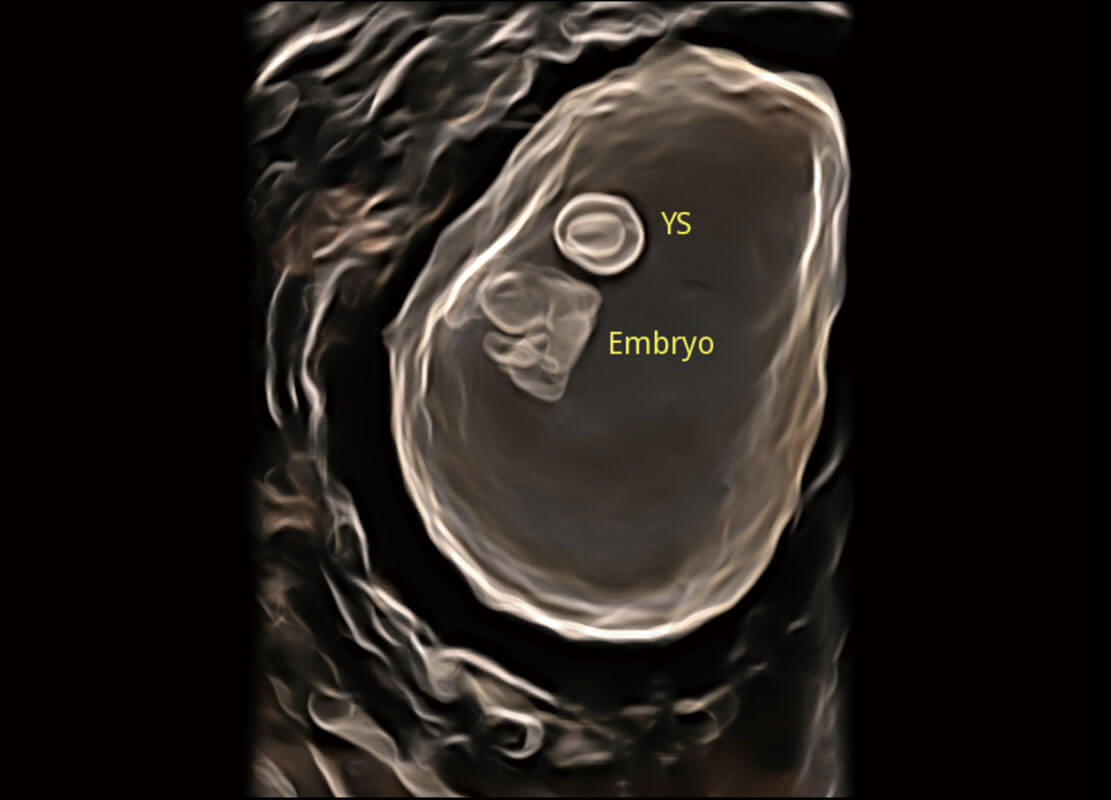

• 高分辨率容积成像-早孕胎儿

• 胎儿体循环

• 光影成像-孕囊